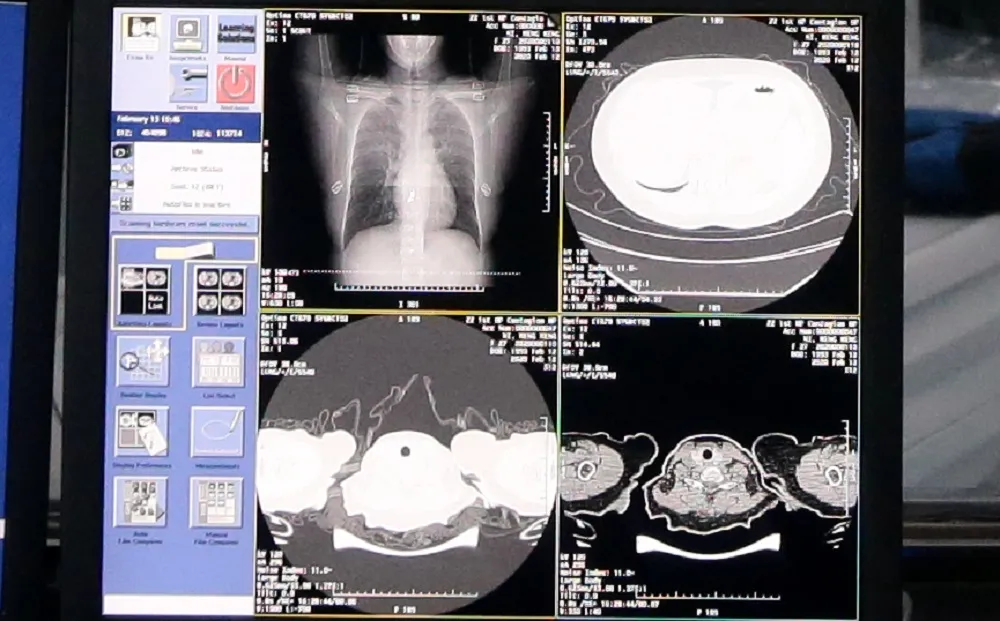

達摩院とアリババクラウドが共同開発した医療AIによる検査画面

新型コロナウイルス(COVID-19)による肺炎流行が続いています。感染者数の増加に伴い、感染しているかを確認する検査も膨大な数になりました。この問題を解決するべく、アリババグループは、研究機関である達摩院(DAMO Academy、以下、達摩院)とクラウドコンピューティングの開発・運用を担うアリババクラウドとの協力により、テクノロジーによる支援ソリューションを開発しました。CT画像から診断する医療AIを開発。20秒以内という短時間で、感染しているかどうかを判断します。その分析精度は96%にまで達しており、診断効率を格段に向上させています。

新型肺炎流行初期には感染例が少なく診断データが不足していたことから、CT画像での診断は困難でした。そこでPCR(核酸増幅法)検査が標準的な診断基準となりました。その後、診断データが増加するにつれ、CT画像での新型肺炎の特徴が明らかになり、今ではこちらが標準的な診断基準とされています。しかし、CT画像による検査にも課題はあります。患者1人当たりのCT画像は約300枚と多く、医師による検査には5分から15分もの時間が必要だったのです。

この医療AIは再帰型ニューラルネットワーク(Recurrent Neural Network、以下RNN)を活用したもので、畳み込みニューラルネットワークによって、新型肺炎に罹患しているかどうかをCT画像から見分けるものです。最終的には1例あたりの検査時間は20秒未満に短縮し、識別精度は96%という高い水準に達しました。また、肺全体に占める病巣部位の比率を測定することで、病状の進行を量的に示すことも可能となりました。